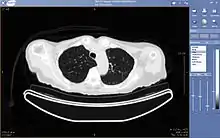

A picture archiving and communication system (PACS) is a medical imaging technology which provides economical storage and convenient access to images from multiple modalities (source machine types).[1] Electronic images and reports are transmitted digitally via PACS; this eliminates the need to manually file, retrieve, or transport film jackets, the folders used to store and protect X-ray film. The universal format for PACS image storage and transfer is DICOM (Digital Imaging and Communications in Medicine). Non-image data, such as scanned documents, may be incorporated using consumer industry standard formats like PDF (Portable Document Format), once encapsulated in DICOM. A PACS consists of four major components: The imaging modalities such as X-ray plain film (PF), computed tomography (CT) and magnetic resonance imaging (MRI), a secured network for the transmission of patient information, workstations for interpreting and reviewing images, and archives for the storage and retrieval of images and reports. Combined with available and emerging web technology, PACS has the ability to deliver timely and efficient access to images, interpretations, and related data. PACS reduces the physical and time barriers associated with traditional film-based image retrieval, distribution, and display.

Most PACS handle images from various medical imaging instruments, including ultrasound (US), magnetic resonance (MR), Nuclear Medicine imaging, positron emission tomography (PET), computed tomography (CT), endoscopy (ES), mammograms (MG), digital radiography (DR), phosphor plate radiography, Visible Light Photography (VL), Histopathology, ophthalmology, etc. Additional types of image formats are always being added. Clinical areas beyond radiology; cardiology, oncology, gastroenterology, and even the laboratory are creating medical images that can be incorporated into PACS. (see DICOM Application areas).

Typically a PACS consists of a multitude of devices. The first step in typical PACS systems is the modality. Modalities are typically computed tomography (CT), ultrasound, nuclear medicine, positron emission tomography (PET), and magnetic resonance imaging (MRI). Depending on the facility's workflow most modalities send to a quality assurance (QA) workstation or sometimes called a PACS gateway. The QA workstation is a checkpoint to make sure patient demographics are correct as well as other important attributes of a study. If the study information is correct the images are passed to the archive for storage. The central storage device (archive) stores images and in some cases reports, measurements and other information that resides with the images. The next step in the PACS workflow is the reading workstations. The reading workstation is where the radiologist reviews the patient's study and formulates their diagnosis. Normally tied to the reading workstation is a reporting package that assists the radiologist with dictating the final report. Reporting software is optional and there are various ways in which doctors prefer to dictate their report. Ancillary to the workflow mentioned, there is normally CD/DVD authoring software used to burn patient studies for distribution to patients or referring physicians. The diagram above shows a typical workflow in most imaging centers and hospitals. Note that this section does not cover integration to a Radiology Information System, Hospital Information System and other such front-end system that relates to the PACS workflow.